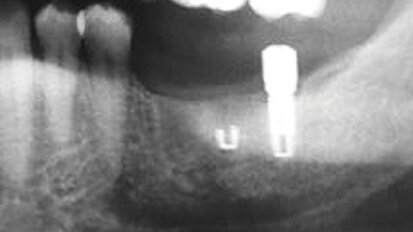

Immediate restoration in the fully edentulous maxilla region

This clinical case required optimal implant placement based upon a restoratively driven treatment plan and guided surgery. To achieve this goal, we made use...